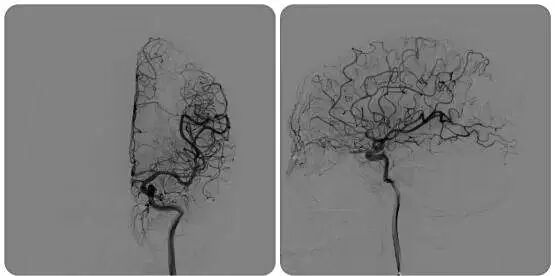

术前照片

面对陈女士这种位置深、体积大、血流量高的复杂型AVM,单一治疗方法往往风险较大或难以彻底清除病灶。针对这类复杂AVM,中山市小榄人民医院神经外科团队制定了周密的 “先栓塞,后切除” 联合治疗方案,这种联合策略也是处理复杂脑动静脉畸形的金标准之一。

术后照片

患者术后恢复良好,已顺利出院。